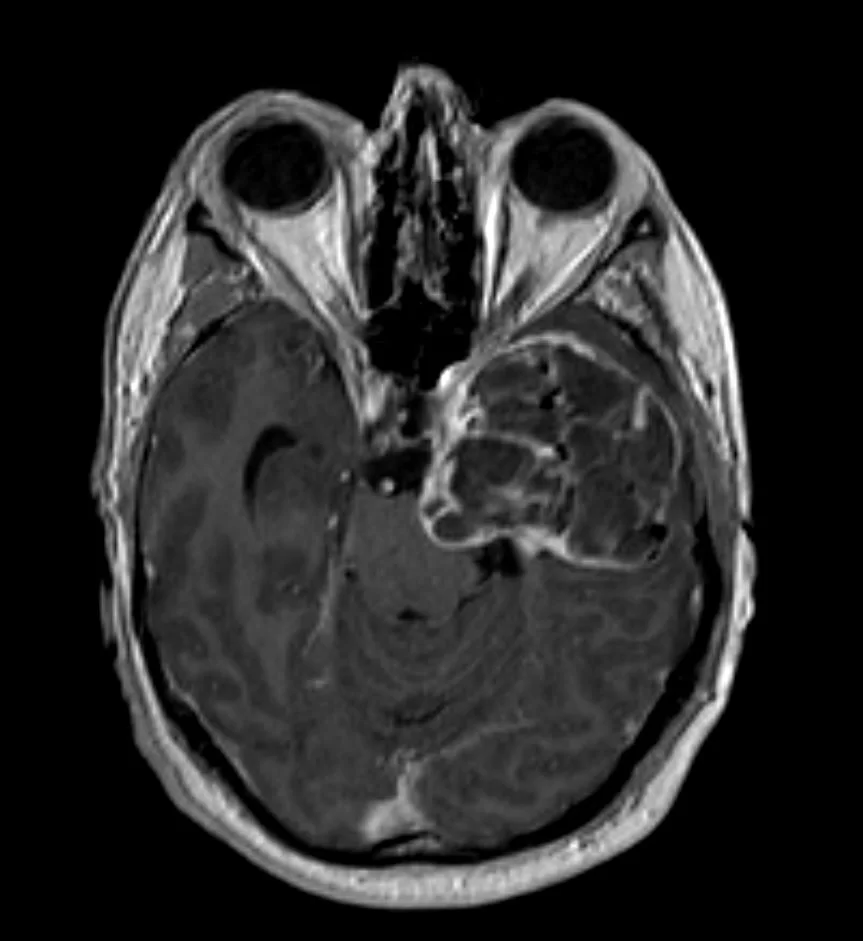

Η μαγνητική τομογραφία εγκεφάλου ανέδειξε εκτεταμένη χωροκατακτητική εξεργασία του μέσου κρανιακού βόθρου, πιθανότατα υποτροπή του δερμοειδούς όγκου για τον οποίο είχε χειρουργηθεί ο ασθενής το 1991.